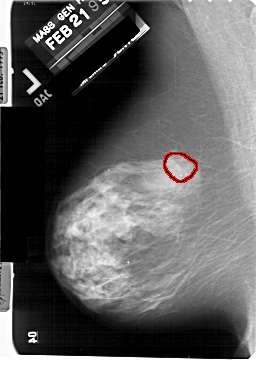

A_1930_1.LEFT_CC

LEFT_CC LINES 5491 PIXELS_PER_LINE 3676 BITS_PER_PIXEL 12 RESOLUTION 43.5 OVERLAY

FILE: A_1930_1.LEFT_CC.OVERLAY

TOTAL_ABNORMALITIES 1

ABNORMALITY 1

LESION_TYPE CALCIFICATION TYPE PLEOMORPHIC DISTRIBUTION CLUSTERED

ASSESSMENT 4

SUBTLETY 3

PATHOLOGY MALIGNANT

TOTAL_OUTLINES 1

BOUNDARY